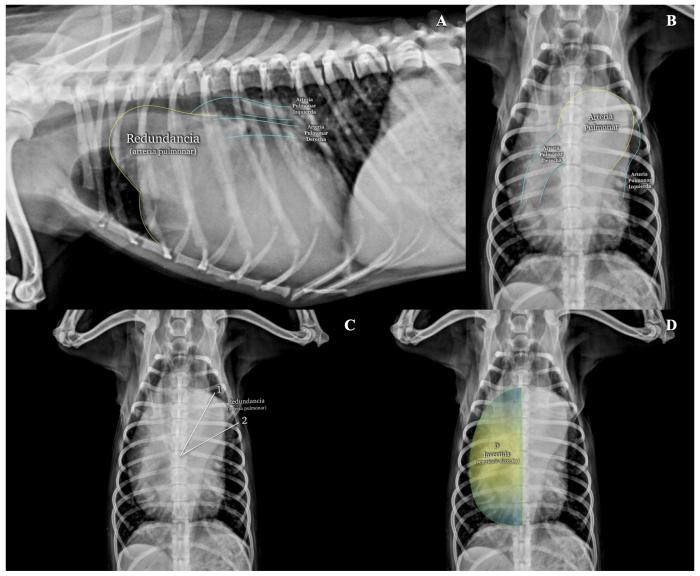

La HP muestra aumento de las cámaras cardíacas derechas (ventrículo derecho, principalmente), de la arteria pulmonar principal y de sus ramas derecha e izquierda. En la imagen laterolateral, el ventrículo derecho se muestra recostado sobre el esternón (ocupando más de 3 esternebras) y la arteria pulmonar muestra una redundancia significativa en la base cardíaca craneal (Figura2A). El par ortogonal muestra D invertida para el ventrículo derecho y redundancia de la arteria pulmonar entre la 1 y las 2, cuando se usa la analogía de las agujas del reloj para establecer aumentos camerales específicos (Figura2B-D). Las arterias pulmonares craneales y caudales, sobre las vistas laterolateral y dorsoventral, respectivamente, pueden evidenciar aumento de su diámetro cuando se comparan con las estructuras costales respectivas7.